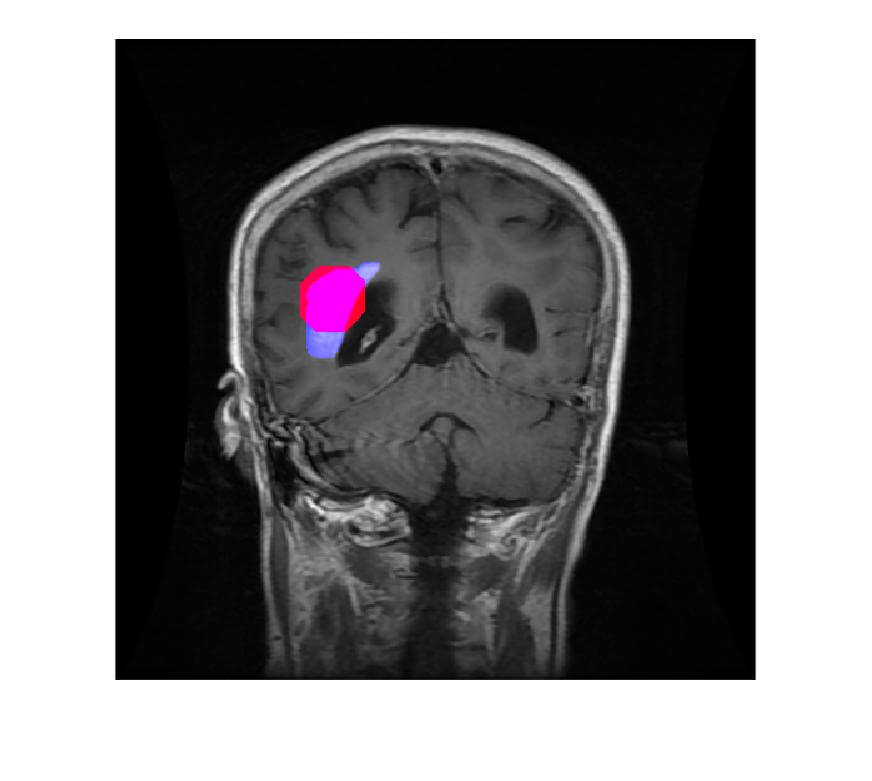

- The extracted tumor will be highlighted in red color and Blue color is the true tumor.